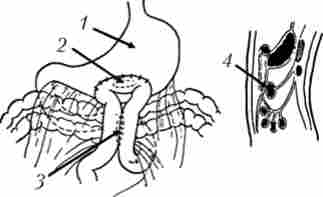

Гепатікоентероанастомоз проводиться в випадках, коли пухлинний інфільтрат поширюється але жовчному протоку в напрямку воріт-печінки, захоплюючи міхуровопротока і залишаючи вільним загальну печінкову протоку або тільки часткові протоки печінки (рис. 21.15). При поширенні пухлини в ворота печінки іноді накладають анастомози звнутрішньопечінковий жовчними протоками.

З метою усунення або попередження виникнення явищ непрохідності ДПК виробляють формування гастроентероанастомоза, частіше - впередіободочного з міжкишкові соустя (рис. 21.16).

Схема операції накладення обхідного гепатікоеюноанастомоз при раку головки підшлункової залози, ускладненому механічною жовтяницею

Мал. 21.15. Схема операції накладення обхідного гепатікоеюноанастомоз при раку головки підшлункової залози, ускладненому механічною жовтяницею. Анастомоз сформований на дренажі, виведеному через анастомозірованной кишку:

Передній впередіободочний гастроентероанастомоз з міжкишкові соустя по Брауну

Мал. 21.16. Передній впередіободочний гастроентероанастомоз з міжкишкові соустя по Брауну: